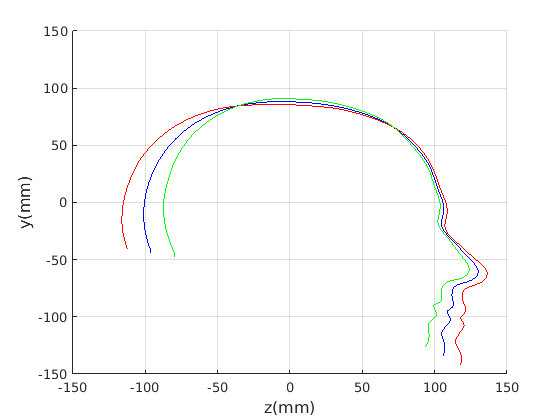

6.2 Model compactness

We evaluate both model construction with geometric alignment (ECN normalisation) and model construction with alignment by Generalised Procrustes Analysis (GPA). Model compactness is a key performance criterion for the correspondence and alignment processes that generate that model [31]. A more compact model has a smaller variance and requires fewer parameters to express a particular shape instance than less compact model. Cumulative variance plots generated by application of PCA are a useful measure of compactness, with more rapidly rising curves indicating more compact models. In Fig. 23 and Fig. 24 we present the cumulative variance plots for our profile models using automatic and manual landmarking respectively and aligned with either ECN or GPA alignment schemes.

Comparing the compactness of the models produced by automatic and manual facial profile landmarking, we found that the performance is almost identical and there is no statistical significance in performance given the modest test size of 100 faces. For example, for the full head profile, with no scale normalisation, the automatic landmarks give cumulative variances of 51.5%, 76.5%, 88.9% and 91.3% over the first four modes whereas the manual landmarks give 50.8%, 76.5%, 88.9% and 91.2%.

A point to note is that whatever model is built, ECN always produces more compact models than GPA. The difference is more marked when a head model is built (cranium and face) compared to cranium only. This can be explained by the fact that the cranium has 210 points sampled on its surface, whereas the face has 128. ECN focusses on aligning the majority group (cranial points) and does not allow more extreme features (such as a large nose) to influence this. GPA on the other hand does, so relatively few points around the nose region can influence alignment over the whole cranium. ECN normalisation is more appropriate when we are interested in cranial shape.